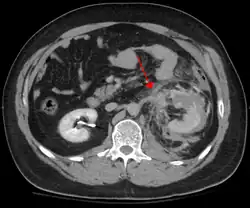

The imaging modality of choice is contrast-enhanced, computed tomography (CT) which is readily available in most emergency departments of moderate or above size. Scan times have become shorter with each generation of scanners and current scans are quick and accurately demonstrate renal injuries together with associated injuries to other abdominal or retroperitoneal organs.

Online calculators have been developed that facilitate grading of renal traumatic injuries based on imaging findings according to AAST (American Association for the Surgery of Trauma) guidelines.[8]

Unlike ultrasound examination (FAST), CT provides anatomic and functional information that allows for accurate grading of the injury which is partly responsible for a growing trend toward conservative management (intravenous fluids, close monitoring, watchful waiting) of renal trauma.[9] Conservative management does not apply in situations where extensive urinary extravasation or devitalized areas of renal parenchyma are found and especially if associated with injuries to other abdominal organs; these cases are complication-prone and much more likely to require surgery. That being said, a retrospective study suggests that primary conservative treatment of blunt kidney rupture seems to lead to less surgery, especially less open surgery, and less blood and renal parenchyma loss, compared to a strategy of initial surgery.[10]